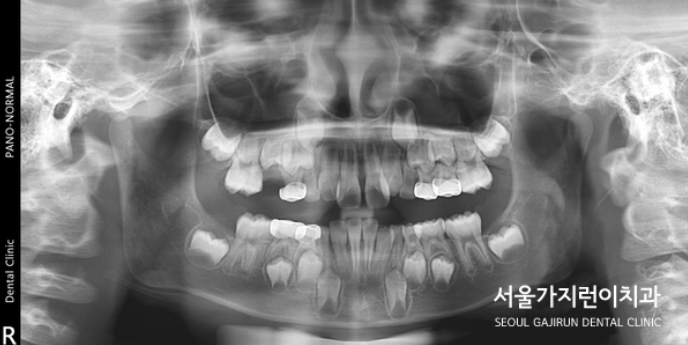

오늘은 상악의 돌출 케이스를 설명해볼텐데요. 치아의 배열 공간이 심하게 부족했던 성장기 환자의 비발치 교정이기 때문에 좀 더 까다로운 교정과정일 수밖에 없었습니다. 환자 분의 경우 상악골의 과성장과 하악골의 열성장이 종합적으로 발현된 케이스로 상악괄의 과성장을 조절하고 상악 견치 및 소구치의 맹출 공간을 확보하기 위해 상악 어금니의 후방이동이 필요했는데요. 그 과정에서 헤드기어라는 장치를 이용한 치아교정이 이루어졌습니다.

이후에는 돌출감을 해소하기 위한 미니스크류를 활용한 치아교정이 이루어졌는데요. (미니스크류는 잇몸에 박혀있는 작은 나사와 같은 장치를 말합니다. ) 미니스크류는 간단한 국소마취로도 식립이 가능하고 잇몸뼈에 직접 식립하기 때문에 강력한 고정힘으로 정밀하게 치아이동이 가능한데요. 치료를 하지 않았다면 치아의 배열이 심하게 비뚤어지고 상악 전치가 뻐드러졌을 것을 1차 성장교정(헤드기어)를 통해 만족할 수 있는 경과를 만들어냈습니다.